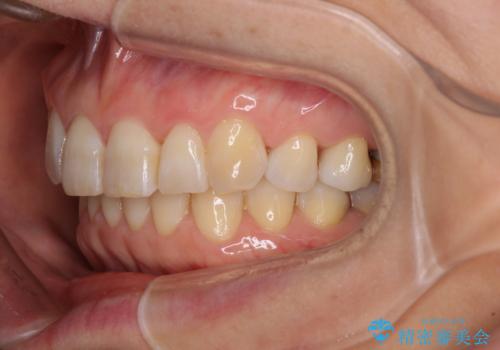

- 前歯のデコボコと上下正中のずれを気にして来院された患者様です。

下顎骨が骨格的にずれがあったため、しっかりと正中を合わせるとなるとワイヤー矯正が必要でしたが、マウスピース矯正を希望されたため、極力正中を合わせることを目標に、インビザラインにて矯正治療を行うこととしました。